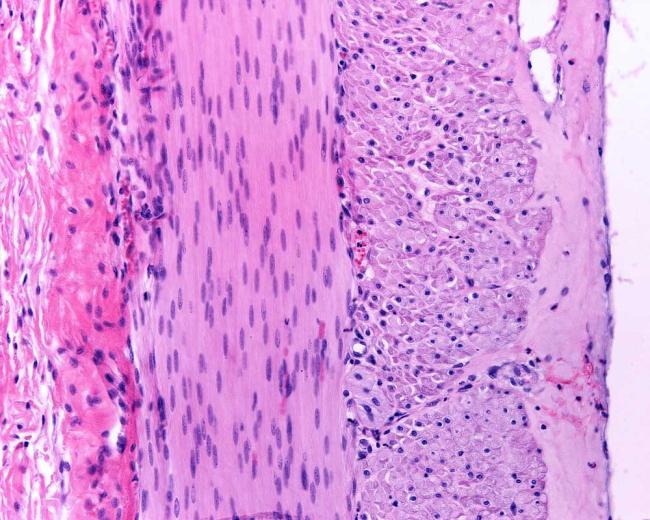

Compared to control mice, substances in the mouse model moved much more slowly through the small and large intestines. This occurred despite no clear defects in the structure of their intestinal tissues.

The team noted that in the small and large intestines of the mouse model, the smooth muscle was thicker than normal. This was not clearly due to differences in muscle cell size or number. It might instead be a result of dysfunctional cell growth and division. The small intestine was also shorter in the mouse model despite there being no differences in body size between the mouse model and control mice.